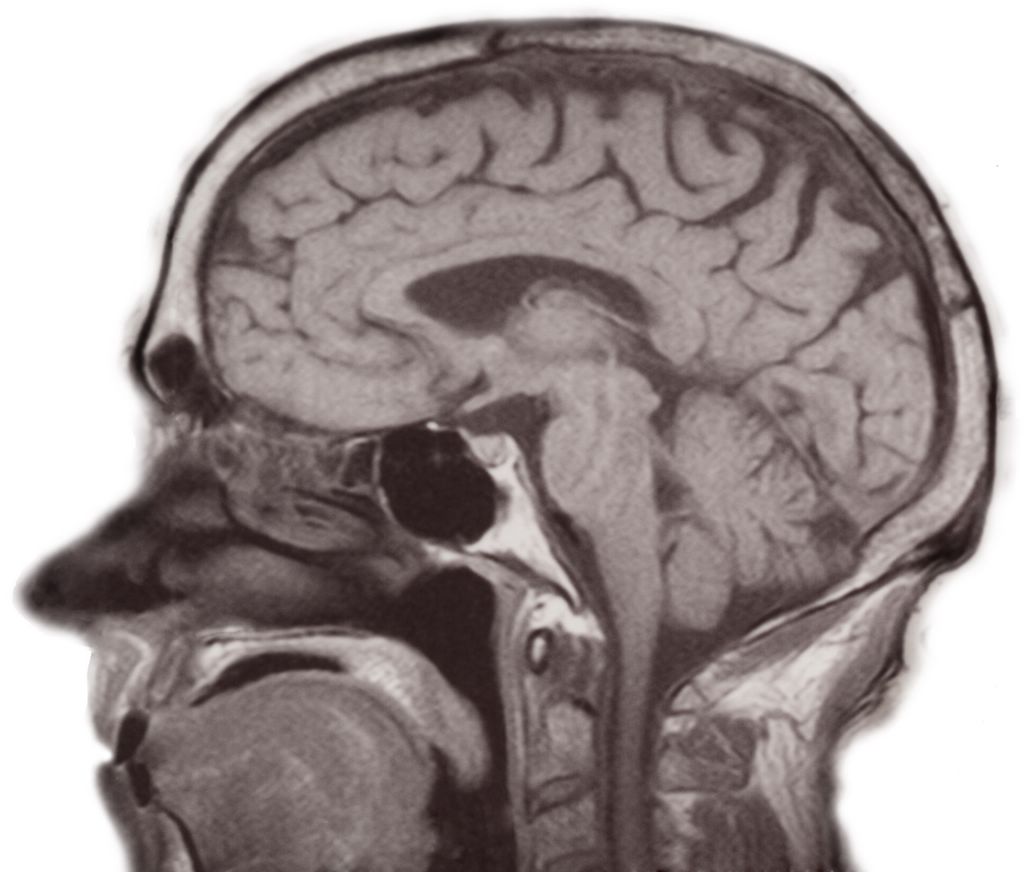

Brains -- mri_11_(was_10).jpg